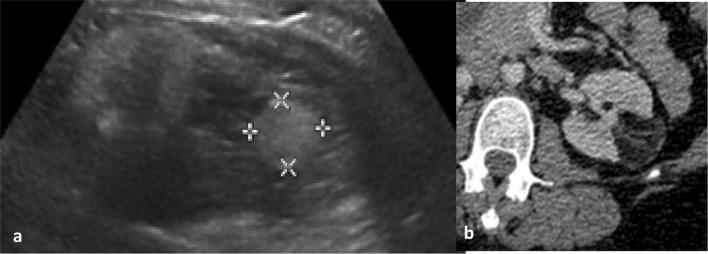

RESULTS

Characterisation of small renal masses (SRM) remains a diagnostic conundrum. Contrast-enhanced ultrasound (CEUS) has been increasingly applied in this field, as have emerging technologies such as multiparametric MRI, radiomics and molecular imaging with technetium-sestamibi single photon emission computed tomography/CT. CT remains the first-line modality for staging of locoregional and suspected metastatic disease. Although the staging accuracy of CT is good, limitations in determining nodal status persist. Response assessment following ablative therapies remains challenging, as reduction in tumour size may not occur. The pattern of enhancement on CT may be a more reliable indicator of treatment success. CEUS may also have a role in monitoring response following ablation. Response assessments following anti-angiogenic and immunotherapies in advanced RCC is an evolving field, with a number of alternative response criteria being proposed. Tumour response patterns may vary between different immunotherapy agents and tumour types; thus, future response criteria modifications may be inevitable.